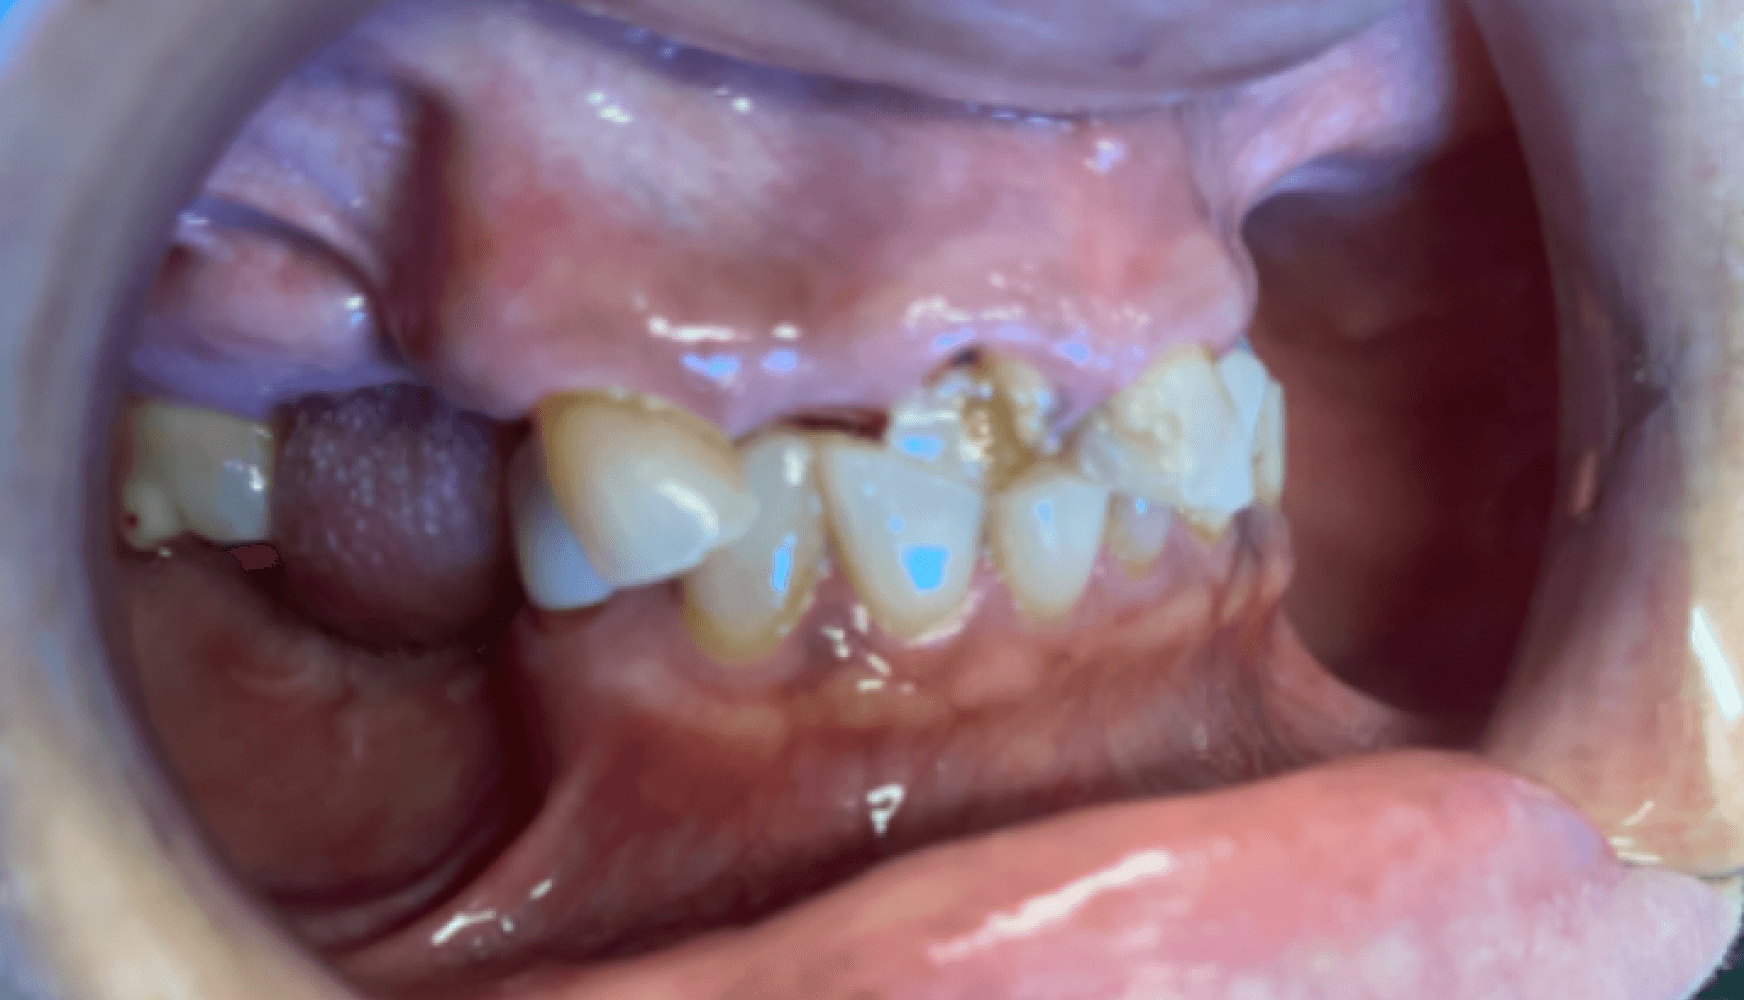

Fig. 1a, 1b, 1c, 1d: The patient’s dentition upon examination reveals significant reduction in VDO, a drastic left-to-right tilt in her smile line, and atrophy of the posterior mandibular ridge.

The patient presented with terminal dentition, multiple compromised and missing teeth, and a significant reduction in vertical dimension of occlusion (VDO) due to years of attrition and bruxism. The patient exhibited a drastic left-to-right tilt in her smile line, with significant atrophy of the posterior mandibular ridge. The right temporomandibular joint (TMJ) displayed a non-reducing disc and deviation to the right upon translation. These anatomical challenges, combined with the patient’s desire for improved function and aesthetics, necessitated a multi-phase treatment plan, beginning with immediate dentures and progressing to implant-supported dentures.